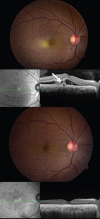

Pregnancy leads to significant changes in the body, which potentially affect the retina. Pregnancy can induce disease, such as that seen in hypertensive retinopathy and choroidopathy. It can cause exudative retinal detachments in the HELLP syndrome (hemolysis, elevated liver enzymes and low platelets), disseminated intravascular coagulation (DIC), and thrombotic thrombocytopenic purpura (TTP), and provoke arterial and venous retinal occlusive disease. Pregnancy may also exacerbate pre-existing retinal disease, such as idiopathic central serous chorioretinopathy (ICSC) and diabetic retinopathy. Special consideration needs to be exercised when treating pregnant patients in choosing medications, as well as in selecting diagnostic modalities and surgical methods.